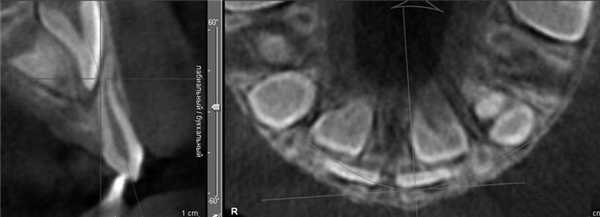

Коронки боковых резцов при значительной инклинации могут камуфлировать небную позицию их корней. Язычное расположение резцов на нижней челюсти (НЧ) наблюдается редко, так как уменьшение ее размеров сочетается с небольшой шириной альвеолярного отростка; чаще корни резцов располагаются плотно друг к другу, как бы исходя своими верхушками из одной точки и расходясь по мере увеличения их мезиодистального диаметра (рис. 3). Рисунок 3. Плотное расположение корней резцов (пациент М.Д.). Такое проявление максимально компактного расположения резцов НЧ описано в литературе как «симптом букета» [1].

После прорезывания зубов форма альвеолярного отростка в поперечном срезе может напоминать песочные часы с сужением, расположенным между апексом корня и базисом челюсти (рис. 10). Рисунок 10. Форма альвеолярного отростка в виде «песочных часов». а — пациент М.Е.; б — пациент З.А.; в — пациент К.О.